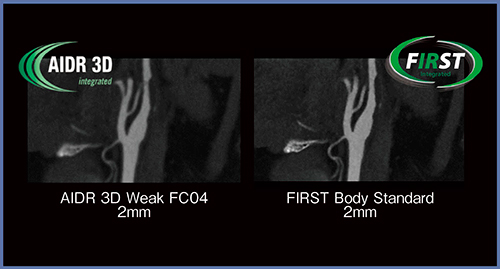

次に,ノイズ抑制目的に軟らかい再構成関数を用い,かつ高い分解能が要求される部位でFIRSTが有効性を発揮するのではないかと考えた。頸部血管では,AIDR 3Dの強度:Weak,再構成関数:FC04と比較して,FIRSTでは血管の辺縁がよりシャープに描出されており,狭窄率の解析における信頼性の向上などが期待できる(図2)。同様に,冠動脈での比較においてもFIRSTの方が高分解能が得られ,末梢血管のCT値が上昇しており,有効性があると考えられた。

図2 頸部血管におけるAIDR 3DとFIRSTの比較